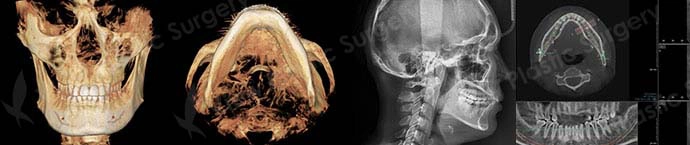

A significant part of how facial contouring surgery works is determined before the operation itself. Through 3D CT scans and X-ray imaging, surgeons analyze bone shape, left–right asymmetry, nerve pathways, and muscle attachment points. Based on this analysis, a personalized adjustment range is designed to match the patient’s overall facial proportions. This process minimizes unnecessary bone removal and helps ensure safety, predictability, and long-term stability.

In Korea, facial contouring surgery has developed into a highly specialized field that considers not only bone reduction but also overall facial proportion and soft tissue response. Because multiple facial structures are often addressed simultaneously, preoperative analysis using 3D CT scans and X-rays is essential. Surgical planning emphasizes long-term stability and balance rather than immediate postoperative appearance.